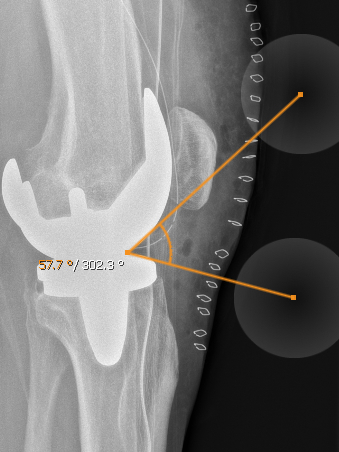

11.1.5. Winkelmessung

Die Winkelmessung erzeugt einen Winkel auf dem aktuellen Schnittbild. Die Geraden des Winkels sind in ihrer Länge und Richtung einstellbar, sodass Sie den Winkel nach Belieben ausrichten können. Sie können den gesamten Winkel durch antippen und halten des Schnittpunktes verschieben. Der Winkel kann im Annotationsmenü gelöscht werden.

Neben dem normalen Winkel gibt es auch den entfernten Winkel. Während der normale Winkel ein echter Winkel ist, berechnet der entfernte Winkel den Winkel zwischen den beiden Geraden, ohne einen Schnittpunkt. Darüber hinaus kann es wie ein normales Winkelwerkzeug verwendet werden.